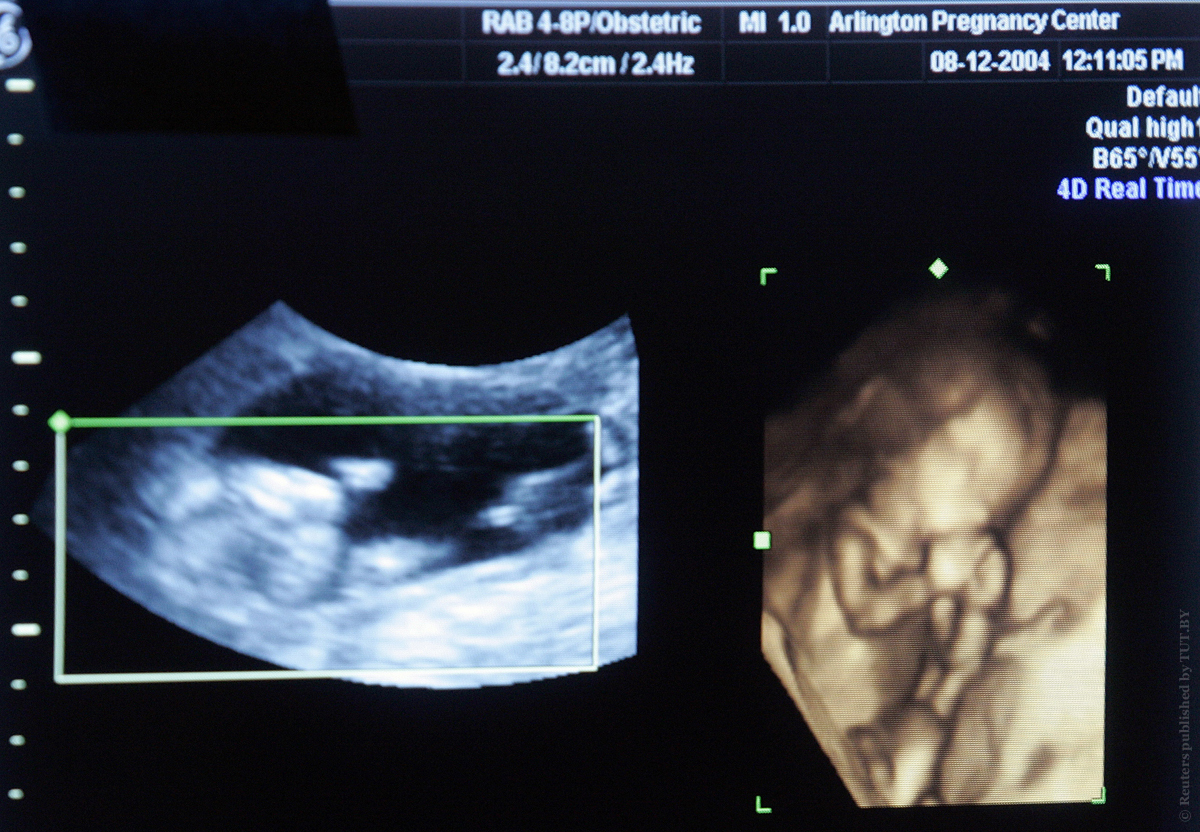

В прошлом году около 1000 детей в Беларуси родились с помощью вспомогательных репродуктивных технологий, в том числе ЭКО.

Фото: Reuters

Людмила Легкая, начальник отдела медицинской помощи матерям и детям Минздрава в Национальном пресс-центре рассказала, что эффективность первой попытки ЭКО в 2018 году была 43,1%, то есть почти у каждой второй женщины получалось забеременеть и родить малыша. Этот показатель сравним с мировым.